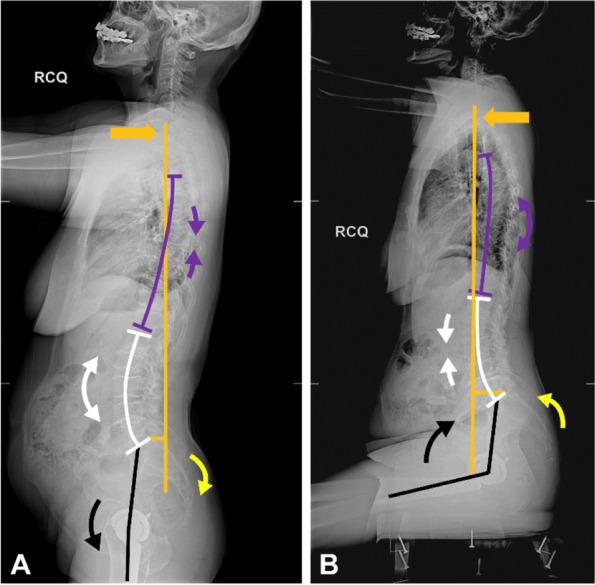

We conducted a retrospective review of consecutive primary THA patients. We measured SVA, spinopelvic parameters (pelvic tilt [PT], pelvic incidence, and sacral slope), thoracic kyphosis (TK), lumbar lordosis (LL), proximal femur angle (PFA), and cup version using functional radiographs of patients in the standing and upright sitting positions. Linear regression was performed to identify parameters related to global trunk alignment change (∆SVA). Spinopelvic stiffness was defined as PT position change < 10°, and a subset of patients with PT change < 0° was categorized into a paradoxical spinopelvic motion group.

One hundred twenty-four patients were analyzed (mean age: 65 years, 61% female). In univariate regression analysis, ∆TK, ∆LL, and ∆PFA were correlated to ∆SVA. In multivariate regression analysis, ΔLL (p < 0.001) and ΔPFA (p < 0.001) were found to be correlated to ΔSVA (ΔSVA = - 11.97 + 0.05ΔTK - 0.23ΔLL - 0.17ΔPFA; adjusted R = 0.558). Spinopelvic stiffness was observed in 40 patients (32%), including five (4%) with paradoxical motion (∆PT = - 3° ± 1°, p < 0.001) with characteristics of balanced standing global trunk alignment (standing SVA = - 1.0 ± 5.1 cm), similar stiffness of the lumbosacral spine (∆LL = - 7° ± 5°), higher hip motion (∆PFA = - 78° ± 6°, p = 0.017), and higher anterior trunk shift (∆SVA = 6.2 ± 2.0 cm, p = 0.003) from standing to sitting as compared to the stiffness group. Two of these five patients experienced dislocation events after THA.

The lumbosacral and hip motions were the major contributors to global alignment postural change. Paradoxical motion is a rare but dangerous clinical condition in THA that might be related to a disproportionally large trunk shift in the stiff lumbosacral spine causing excessive hip motion. In paradoxical motion, diminishing functional acetabular clearance during position change might pose the prosthesis at higher risk of impingement and instability than spinopelvic stiffness.

我们对连续的原发性 THA 患者进行了回顾性研究。我们测量了站立位和直立坐姿位时 SVA、脊柱骨盆参数(骨盆倾斜度[PT]、骨盆入射角和骶骨倾斜度)、胸腰椎后凸角(TK)、腰椎前凸角(LL)、股骨近端角(PFA)和杯倾斜度。使用线性回归来确定与整体躯干对线变化(ΔSVA)相关的参数。脊柱骨盆僵硬度定义为 PT 位置变化<10°,PT 变化<0°的亚组患者被归类为反常脊柱骨盆运动组。

共分析了 124 例患者(平均年龄:65 岁,61%为女性)。在单变量回归分析中,ΔTK、ΔLL 和 ΔPFA 与 ΔSVA 相关。在多变量回归分析中,ΔLL(p<0.001)和 ΔPFA(p<0.001)与 ΔSVA 相关(ΔSVA=-11.97+0.05ΔTK-0.23ΔLL-0.17ΔPFA;调整后的 R=0.558)。40 例(32%)患者出现脊柱骨盆僵硬,其中 5 例(4%)出现反常运动(ΔPT=-3°±1°,p<0.001),具有平衡的站立位整体躯干对线特征(站立位 SVA=-1.0±5.1cm),腰骶脊柱僵硬度相似(ΔLL=-7°±5°),髋关节活动度更高(ΔPFA=-78°±6°,p=0.017),从站立位到坐位时,前躯干移位更大(ΔSVA=6.2±2.0cm,p=0.003)。这 5 例患者中有 2 例在 THA 后发生了脱位事件。

腰骶部和髋关节运动是导致整体对线姿势变化的主要因素。反常运动是 THA 中一种罕见但危险的临床情况,可能与僵硬的腰骶脊柱中躯干过度移位导致髋关节活动度过大有关。在反常运动中,在位置变化过程中功能髋臼间隙减小可能会使假体面临更高的撞击和不稳定风险,而不是脊柱骨盆僵硬。